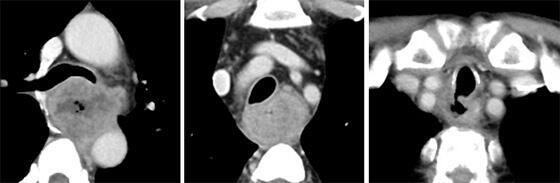

腹臥位胸腔鏡下食道切除術で低侵襲に治療

当科では、白石治先生が積極的に低侵襲食道切除術に取り組み、高度進行がんでも胸腔鏡の拡大視と低侵襲性を最大限に活用して切除しており、ほぼ全例が鏡視下による低侵襲手技で手術が完結しています。特に左側に高度進行した食道がん症例に対しては、白石先生が考案して積極的に応用している左右の胸腔から胸腔鏡下に剥離を行い、安全かつ良好な視野の下で手術を行うことで治癒切除率の向上を図っています。